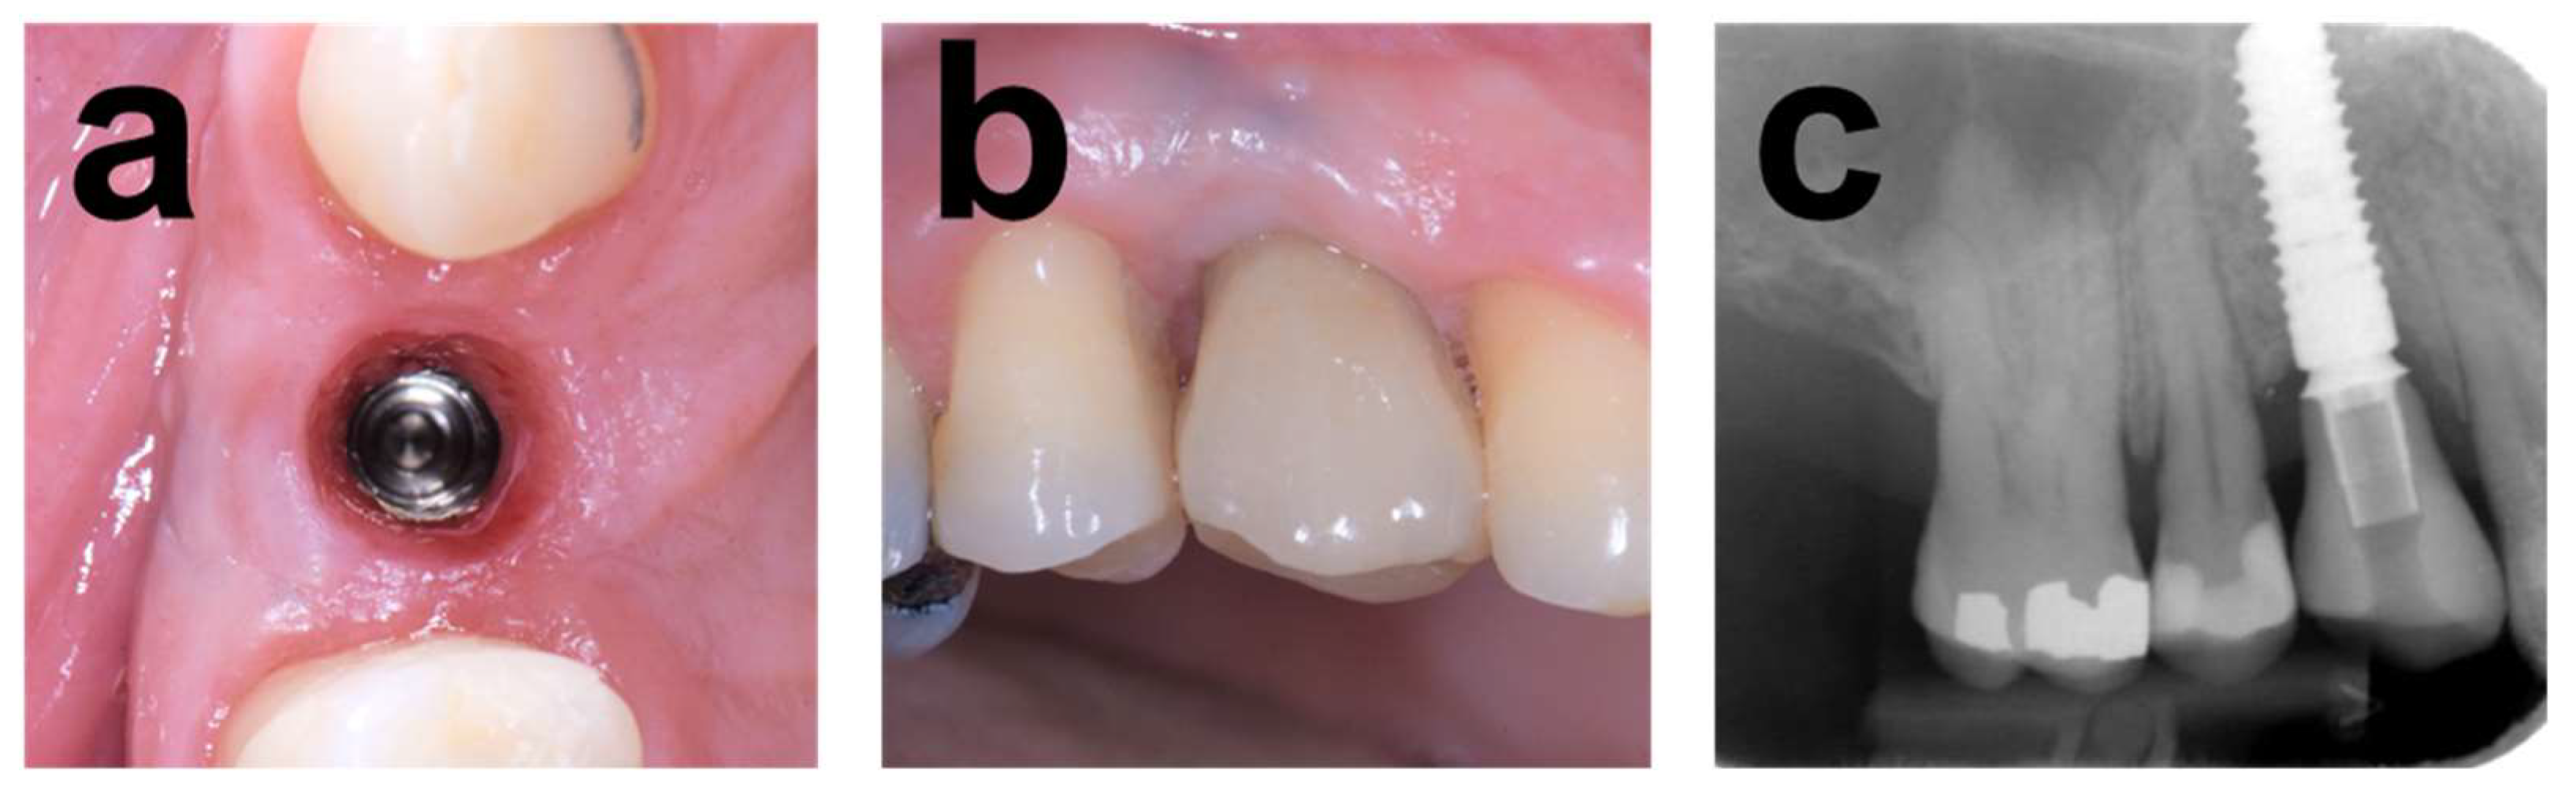

2.7.1. Case 1

2.7.2. Case 2

2.7.3. Case 3